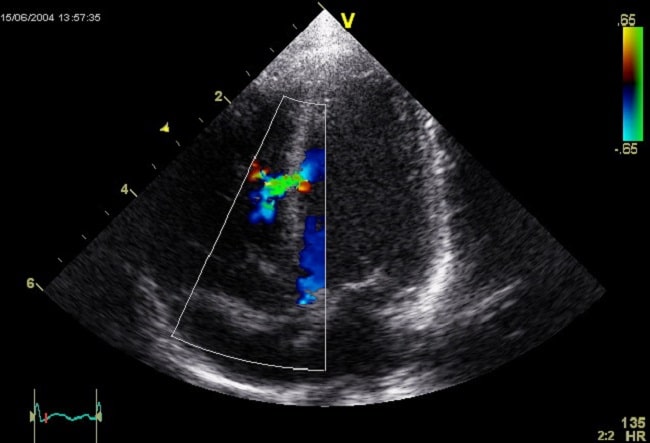

Diagnosis VSD ditegakkan dengan pemeriksaan echocardiography. Echocardiography dua dimensi dengan Doppler biasanya cukup untuk melakukan diagnosis, mengidentifikasi lokasi defek, dan mengestimasi besarnya shunt.

Echocardiography

Echocardiography, biasanya transthoracic atau color Doppler pada VSD dilakukan untuk mengkonfirmasi keberadaan, ukuran, dan lokasi defek septum ventrikel dan memberikan informasi untuk merencanakan prosedur pembedahan.[4]

Pemeriksaan penunjang ini selain membantu mendiagnosis, tapi juga membantu mengevaluasi hemodinamik pada VSD. Echocardiography juga dapat mengidentifikasi peningkatan tekanan arteri pulmonalis, obstruksi right ventricular outflow tract (RVOT), insufisiensi aorta, dan distorsi katup atau valve distortion.[4]

Gambar 3. Ventricular Septal Defect pada Gambaran Echocardiography

Echocardiography transesofageal (TEE) kadang diindikasikan jika ekokardiografi transtorakal tidak memadai. Pemeriksaan TEE juga dapat digunakan intraoperatif untuk membantu menilai tingkat perbaikan, adanya lesi sisa, atau untuk panduan selama penempatan perangkat operatif.[4]